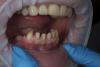

Art 7 Опубликовано 29 марта, 2013 Поделиться Опубликовано 29 марта, 2013 стираемость всех фронтальных зубов,долго время носил бюгель на нч. потом перестал носить и ходил спокойно стирал зубы.ситуация допрепарирование в два этапа сперва низ затем верхкоронки на моделяхв полости ртаоттиски 10 Ссылка на комментарий

Rtov Опубликовано 29 марта, 2013 Поделиться Опубликовано 29 марта, 2013 стираемость всех фронтальных зубов,долго время носил бюгель на нч. потом перестал носить и ходил спокойно стирал зубы.ситуация допрепарирование в два этапа сперва низ затем верхкоронки на моделяхв полости ртаоттискиПреп. оч старательный,здорово! А вот вкв по границе не совсем прецизионно или мне показалось? Ссылка на комментарий